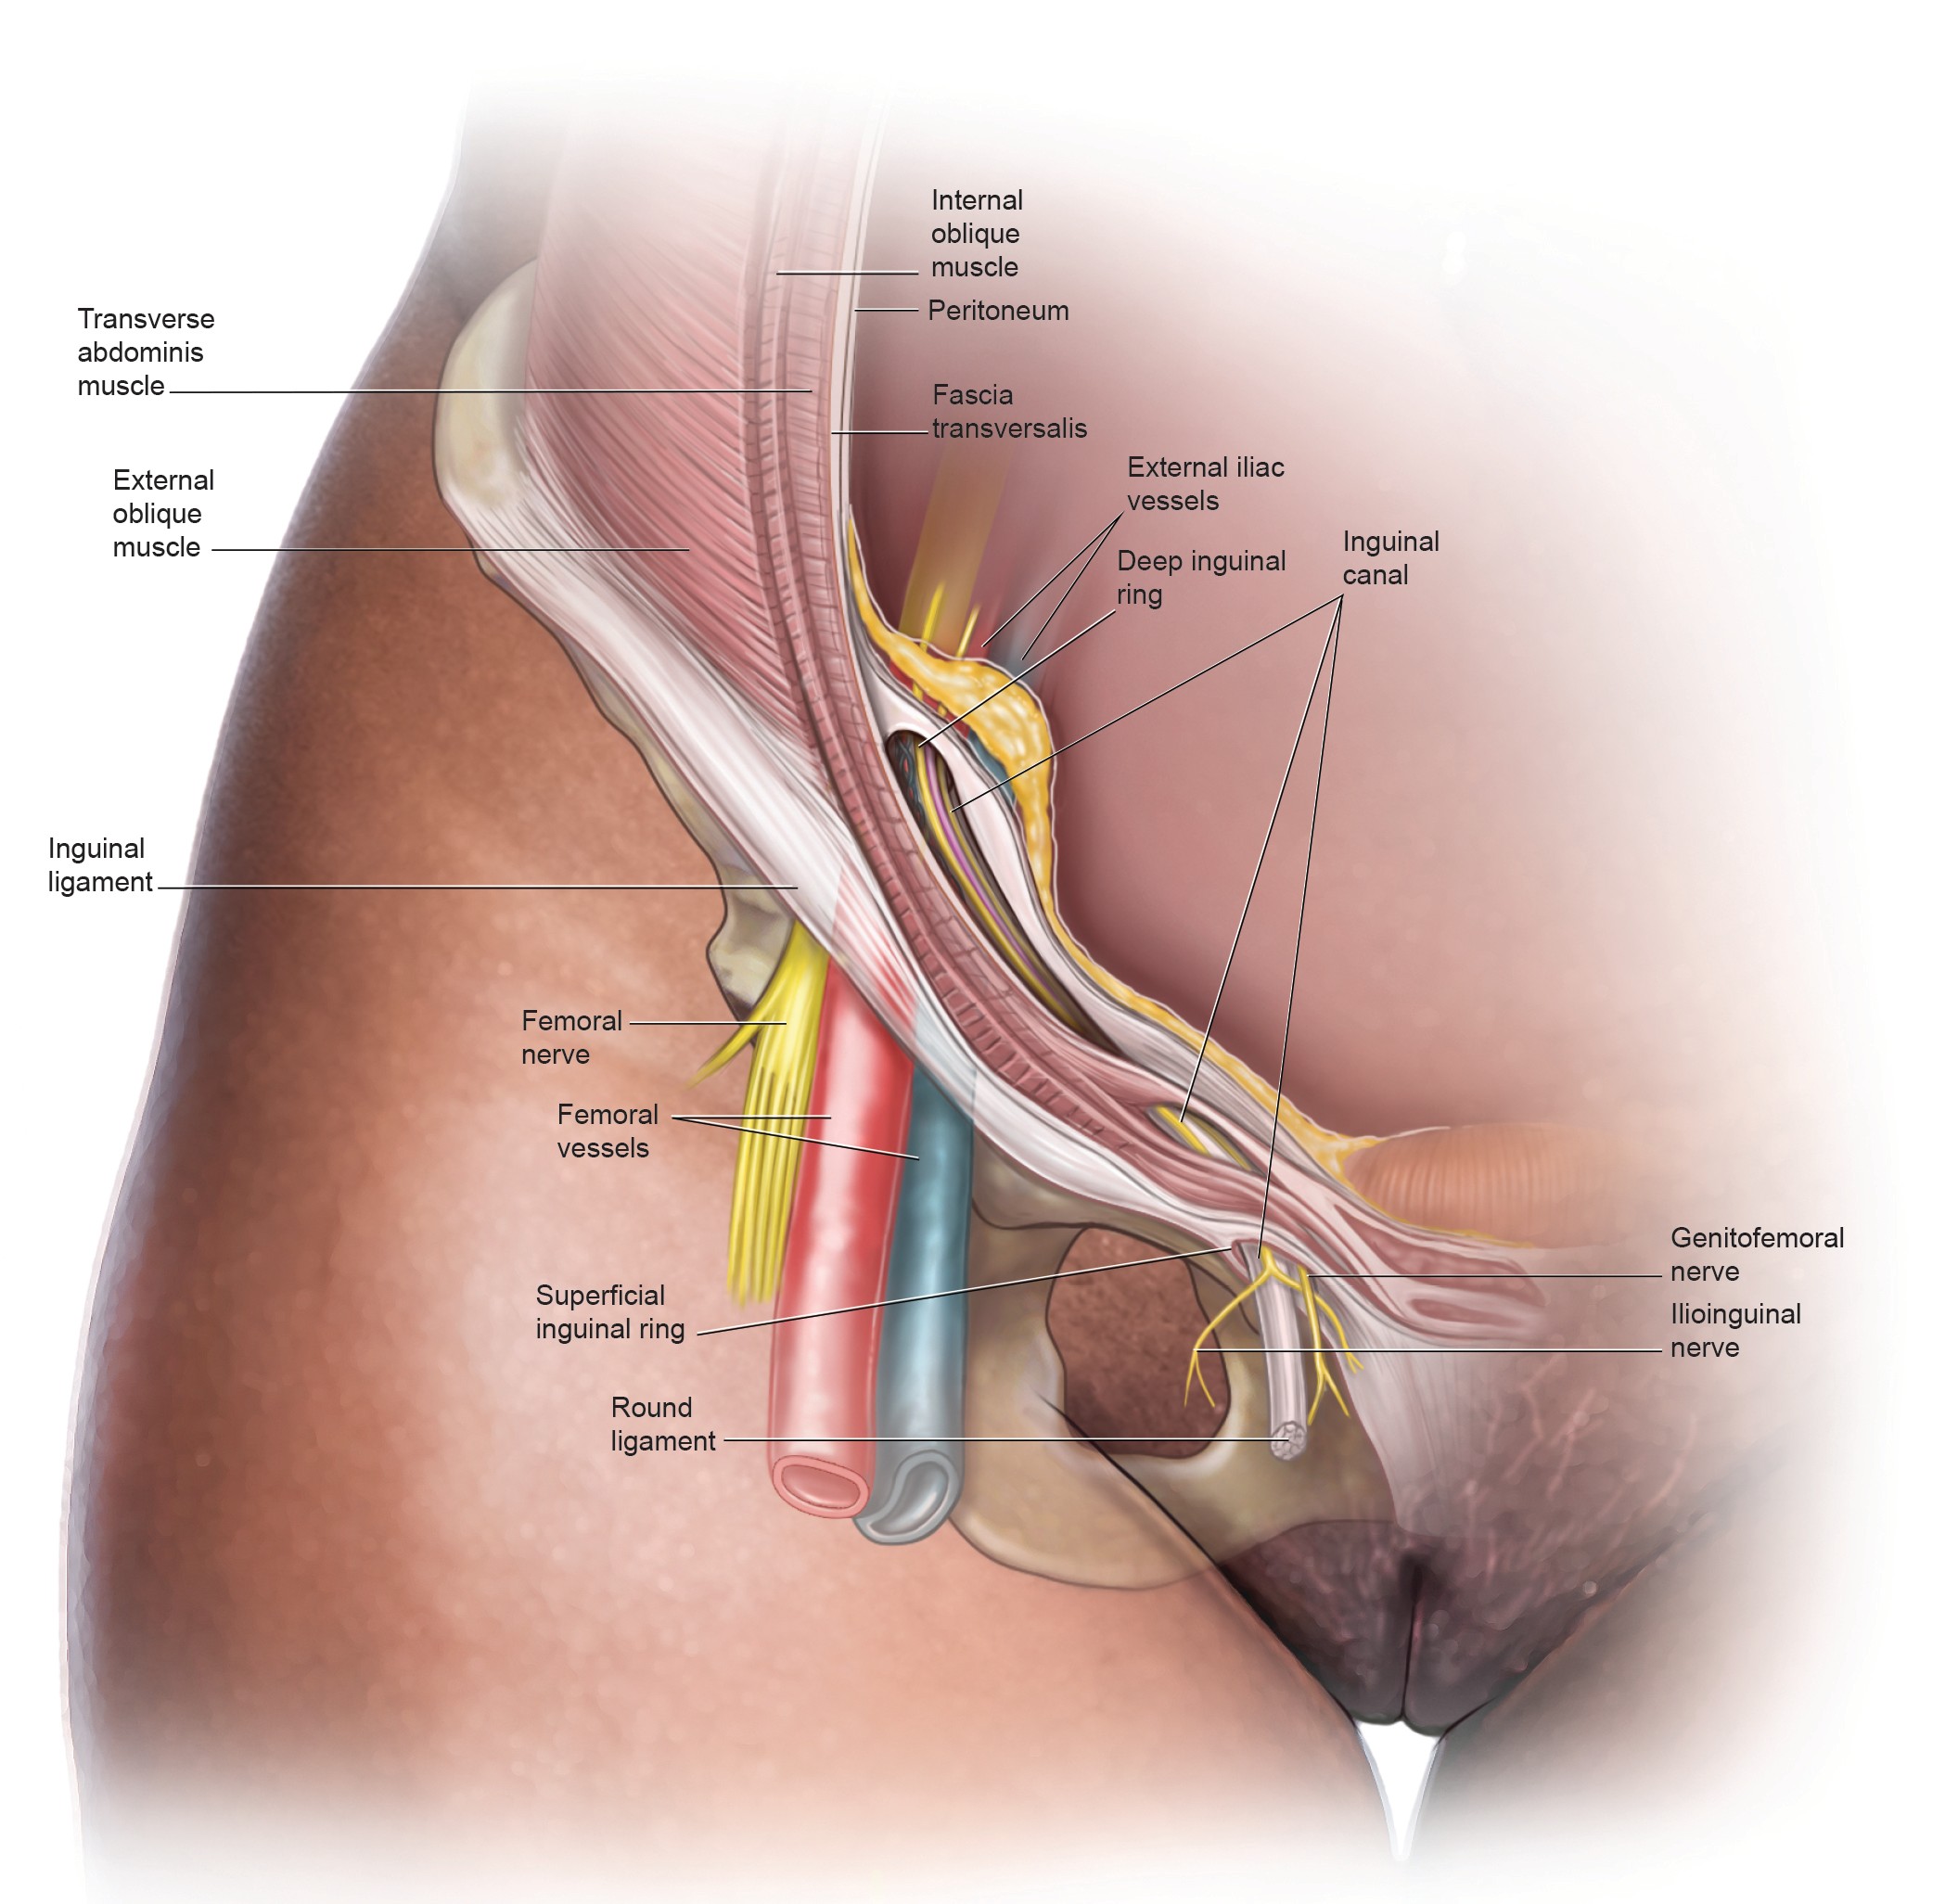

I am a medical illustrator! I wanted to be a doctor and was enrolled in premed, then received a few flyers for colleges in the mail for medical illustration. I decided to change my major from premed to medical illustration. I studied at two private colleges in a combined program for art and medicine.

I create medical illustrations, animations, interactive projects and timelines for physicians, attorneys, medical device and pharmaceutical companies to create illustrations for educational purposes.

I work a lot with attorneys to create medical demonstrative aids for insurance adjusters, mediations and trials. These medical demonstratives help to secure settlements for severely injured and families of decedents.

I am proud to educate people. To scientifically visualize what’s unseen by the naked eye for the general public!

Image Credits

Lindsay Coulter